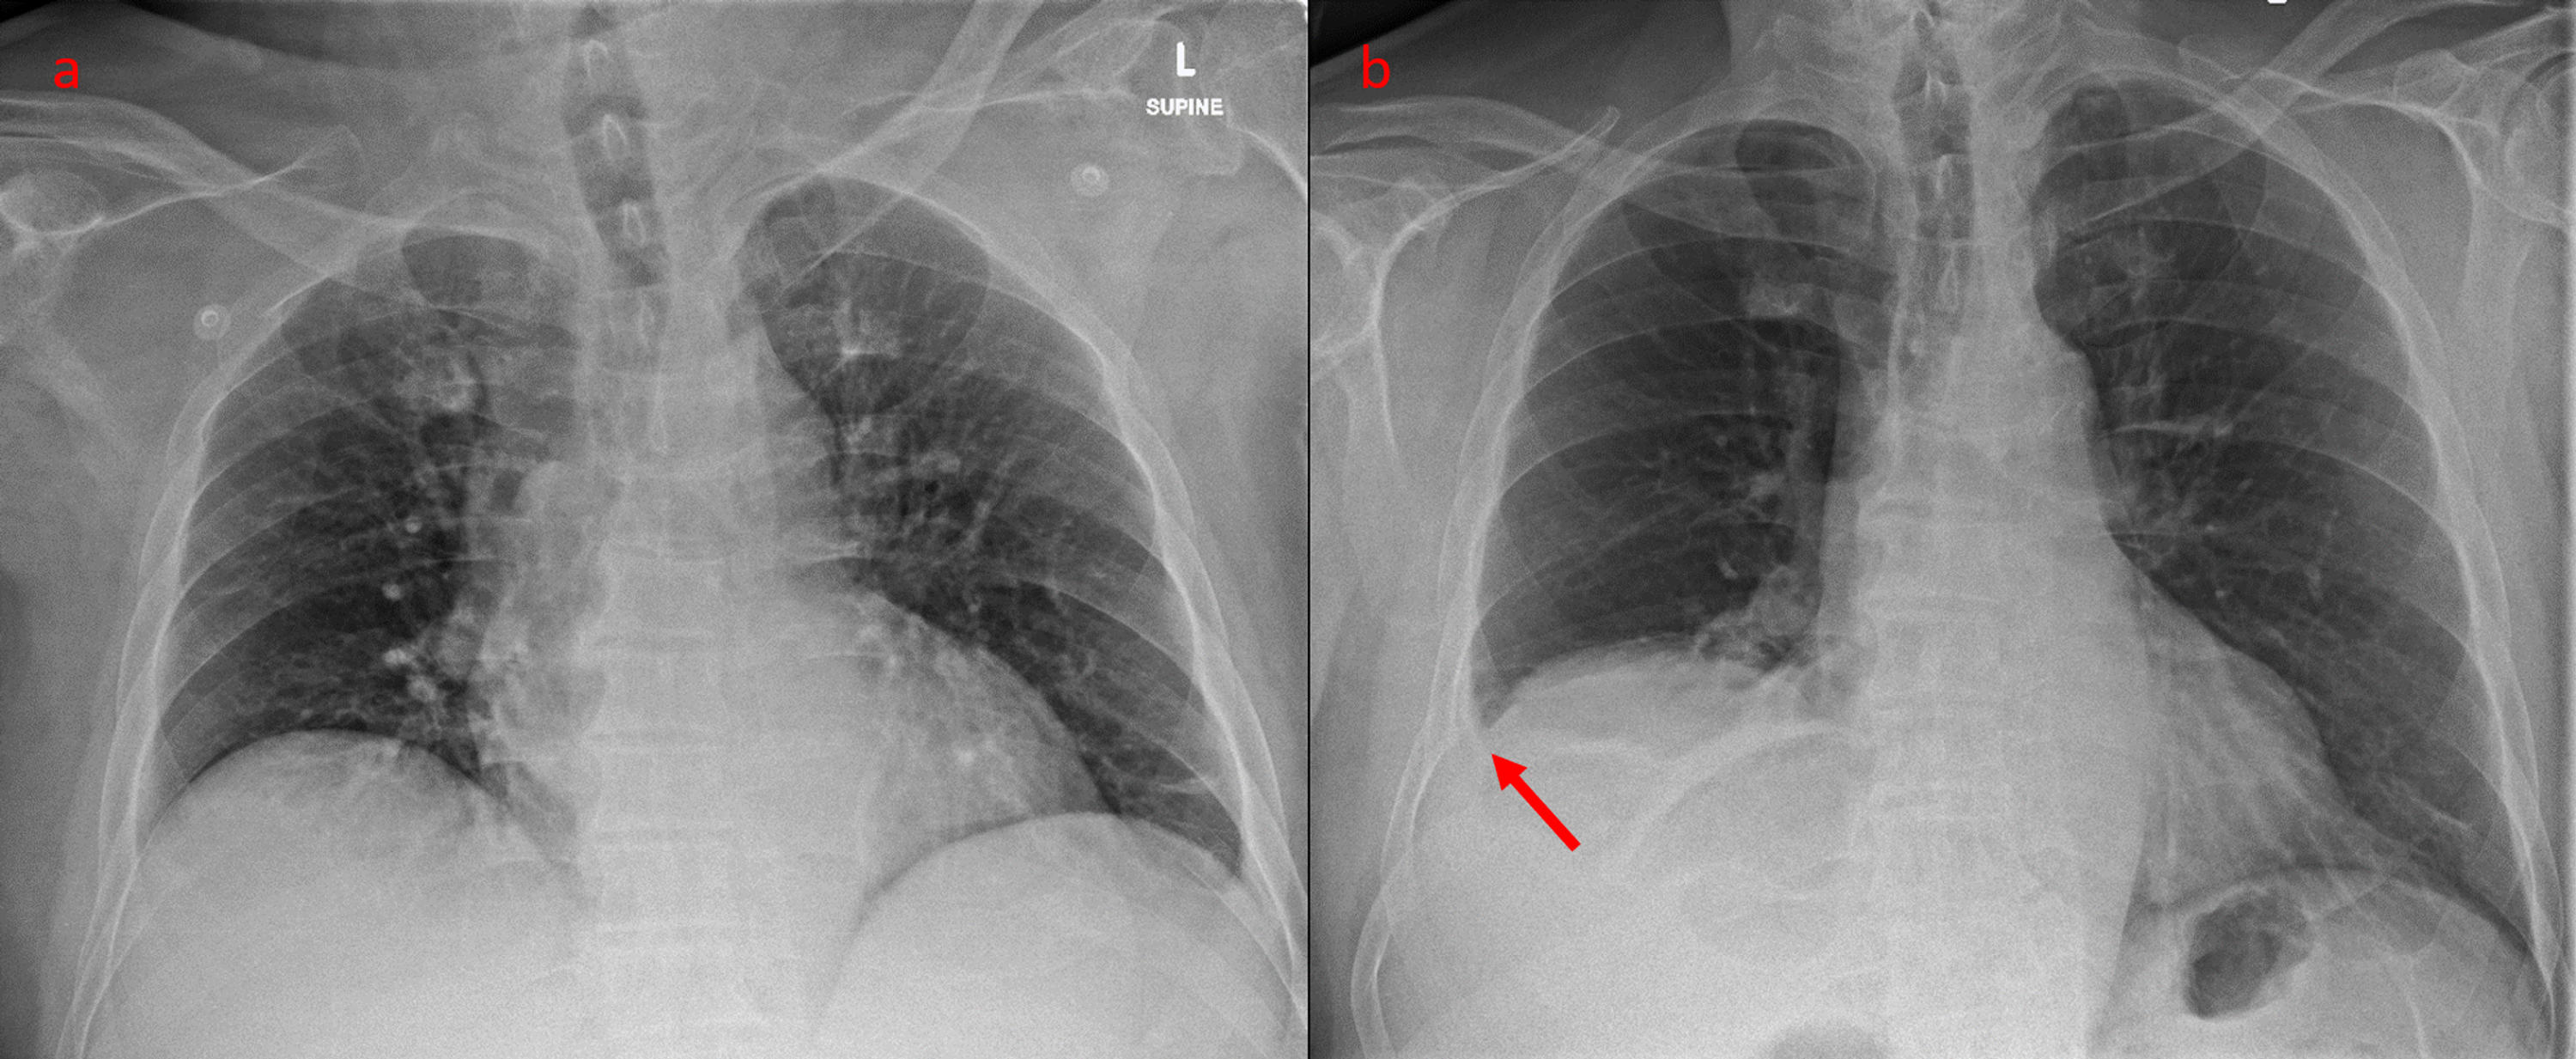

Pneumoperitoneum and subphrenic abscess are two important differential diagnosis of this radiographic sign which can be excluded out when normal plicae circulares or haustral markings of the colon is seen under the right diaphragm. If youre experiencing mild discomfort in your diaphragm take a few minutes to concentrate on deep breathing. Treatment depends on the type of hiatal hernia you have and on your symptoms.

Place one hand on your abdomen and breathe deeply. Reduced number of alveoli air sacs required for normal breathing. In severe cases when there is no simple treatment that can relieve dyspnea your doctor may prescribe morphine. Congenital diaphragmatic hernia CDH. There is usually a long history of heavy smoking. Shortness of breath may be accompanied by wheezing. Diaphragmatic dysfunction caused by transverse myelitis or leukemic infiltration of the cervical spinal cord in a patient with leukemia and shortness of breath. To treat phrenic nerve irritation This condition can be managed with a breathing pacemaker which takes over the responsibility of sending messages to the diaphragm. The cause for shortness of breath was thought primarily due to stable angina on tread mill test positive finding but Chilaiditis syndrome should also be considered as a cause for the shortness of breath.

The rise in intraabdominal pressure further increases intrathoracic and lung volume by pushing the lower rib cage outward. In severe cases when there is no simple treatment that can relieve dyspnea your doctor may prescribe morphine. Diaphragmatic dysfunction caused by transverse myelitis or leukemic infiltration of the cervical spinal cord in a patient with leukemia and shortness of breath. Diaphragmatic plication a surgical procedure that pulls the diaphragm down by introducing a repeated series of continuous sutures across the diaphragm and pulling the muscle taut. A bedside fan or open window with a breeze are also simple but very effective treatments to lessen dyspnea. Depending on the severity of injury to the diaphragm some doctors recommend non-surgical options to treat the breathing issues associated with diaphragm weakness and paralysis. P E Pulmonary embolism.